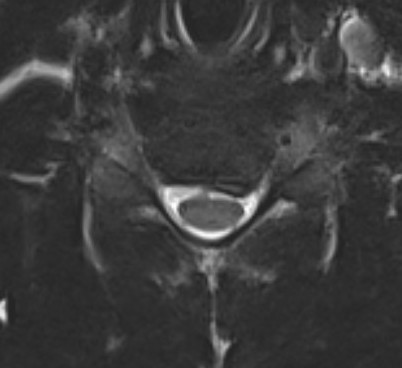

Paracentral disc

Foraminal disc